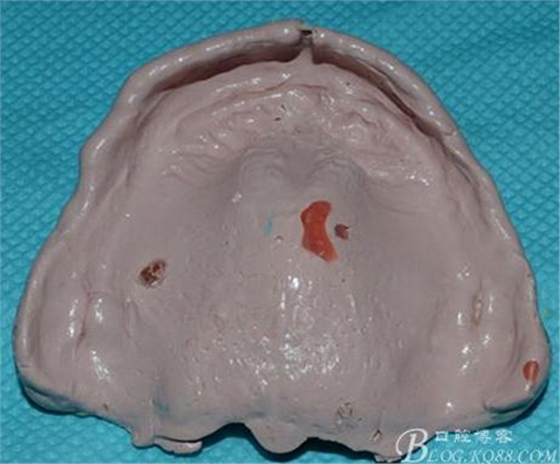

印模取出來(lái)有兩個(gè)大氣泡和幾個(gè)小氣泡。。。但是!組織面的細(xì)節(jié)啊。。。邊緣那個(gè)細(xì)膩完美啊。。。

請(qǐng)無(wú)視略過(guò),注意力細(xì)節(jié)表現(xiàn)~~~

簡(jiǎn)易圍模后完成的最終模型: